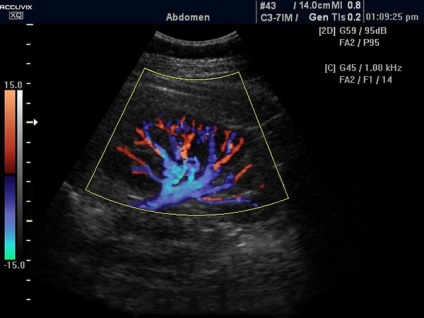

Doppler ultrahang magában helyét azonosító renalis vascularis forgalomban, azok jellemzőit, és meghatározzuk a vér sebességét. Ezzel a módszerrel a tanulmány lehet állítani a következő vesebetegség:

- keringési zavarok, csökkent vaszkuláris integritás;

- vérrögök és ateroszklerotikus plakkok;

- artériák szűkülete.

Normál véráramlás sebessége minősül 50-150 cm / sec. Patológiai a vese erek láthatóvá a monitoron világos színű, ami jelzi a szűkület. Ezen felül, a Doppler-detektált index ellenállást a véráramlásra. A norma ez a mutató tekinthető: 0,7 a veseartéria és 0,34-0,74 számára interlobar artériák.